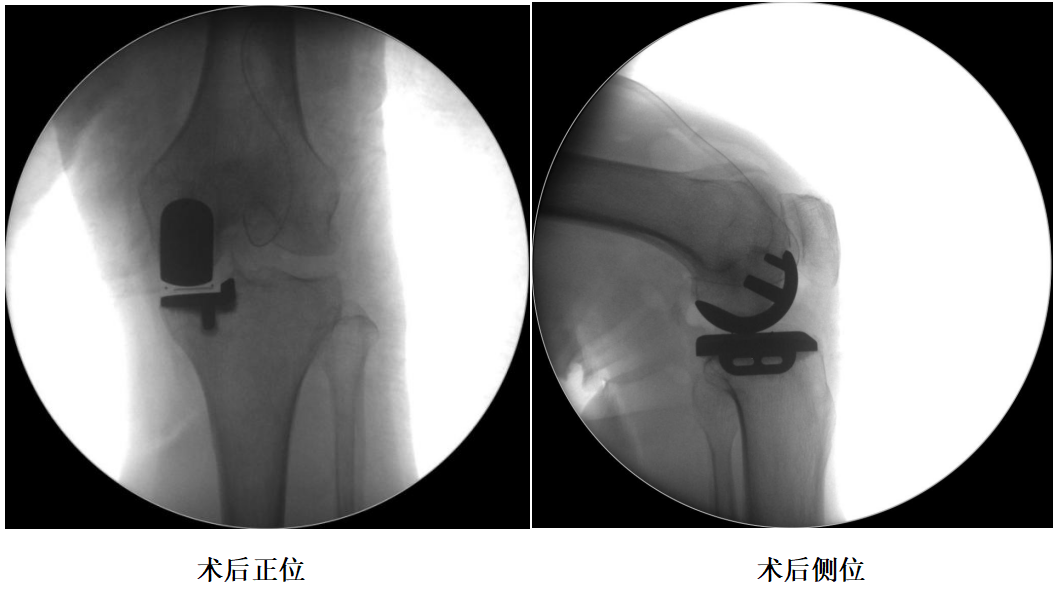

术前透视片

四、术后X片